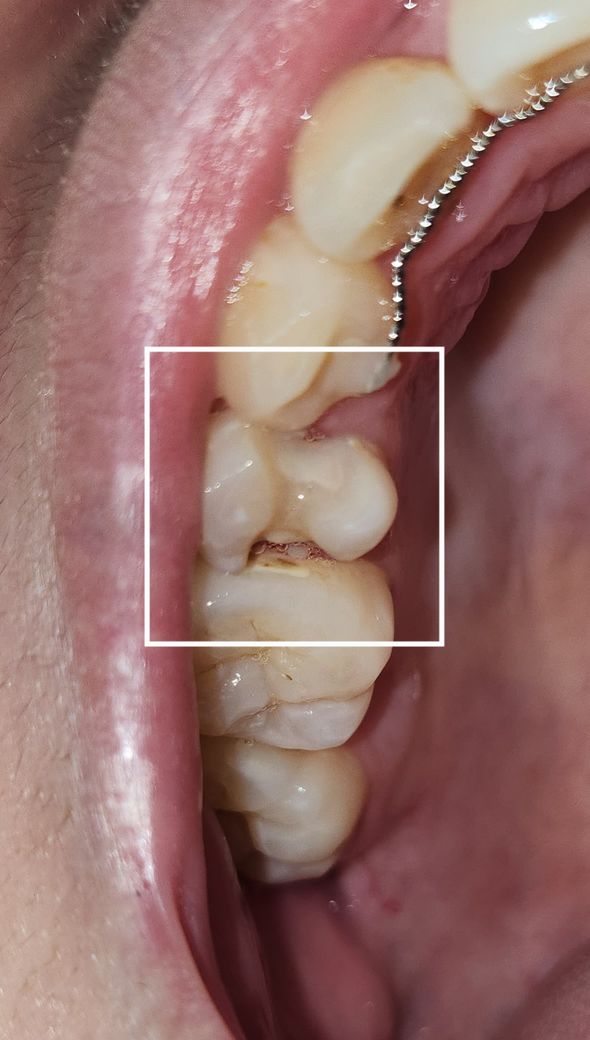

윗니 작은어금니가 깨졌습니다 많이 심각한가요

고구마 말린걸 먹다가 와그작 소리와 함께 이빨이 깨졌습니다

양쪽 이빨과 맞닿은 옆면이 깨져서 정면에서 봤을땐 멀쩡한데 혀를 대보면 텅텅 빈 느낌입니다ㅠㅠ

정중앙은 살아있고 양쪽이 패인듯이 깨졌어요..

현재 통증이나 시림은 전혀 없습니다..양치도하고 물도 마셔봤는데 깨진 부분에 뭐 닿아도 전혀 아무 느낌도 없어요

깨진 부분이랑 떨어져 나온 조각들 사진 올립니다...

예전에 치료한 부분이 깨진거 같습니다. 최소 인레이 또는 크라운 치료를 하셔야될것같습니다.

사진 상 꺠진 부위가 크기 때문에 최소 인레이 치료가 필요해보이며 상태에 따라 크라운 등으로 넘어갈 수 있습니다.

이전에 치료를 한 보철물이 탈락한것으로 보입니다.

이런경우에 보철물을 다시 제작하거나 크라운 치료를 할수 있습니다.

일단은 사진상 판단은 어려우나 이전에 충치치료했던게 깨졌을 가능성이 높습니다 다행히 신경이 노출되지 않았다면 신경치료는 안하더라도 깨진부분은 크라운으로 씌워 치아를 보호해야합니다